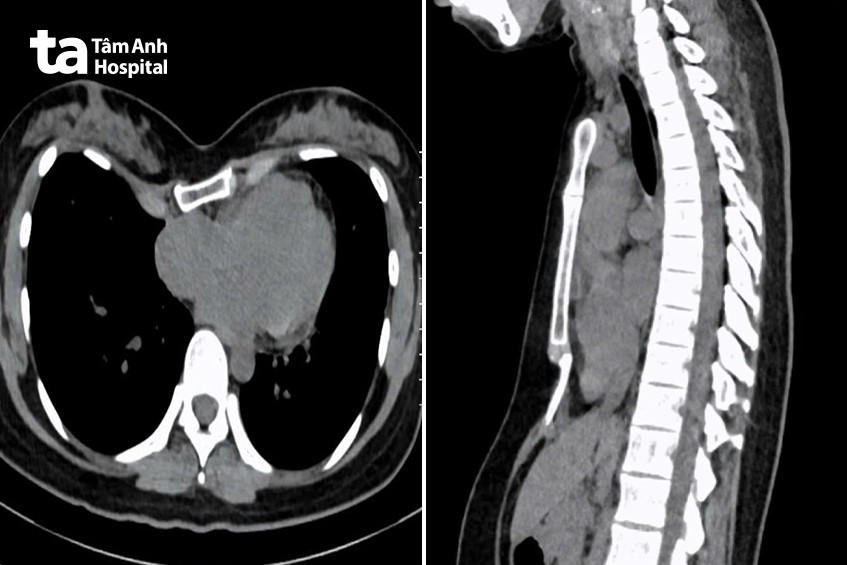

ThS.BS.CKI Phạm Ngọc Minh Thủy, khoa Ngoại Tim mạch, Trung tâm Tim mạch, cho biết chị Tây lõm ngực nặng, lệch về bên phải, chụp cắt lớp vi tính ghi nhận chỉ số Haller là 5,2 (tỷ lệ giữa đường kính ngang và đường kính trước sau của ngực, bình thường chỉ số này dưới 2,5).